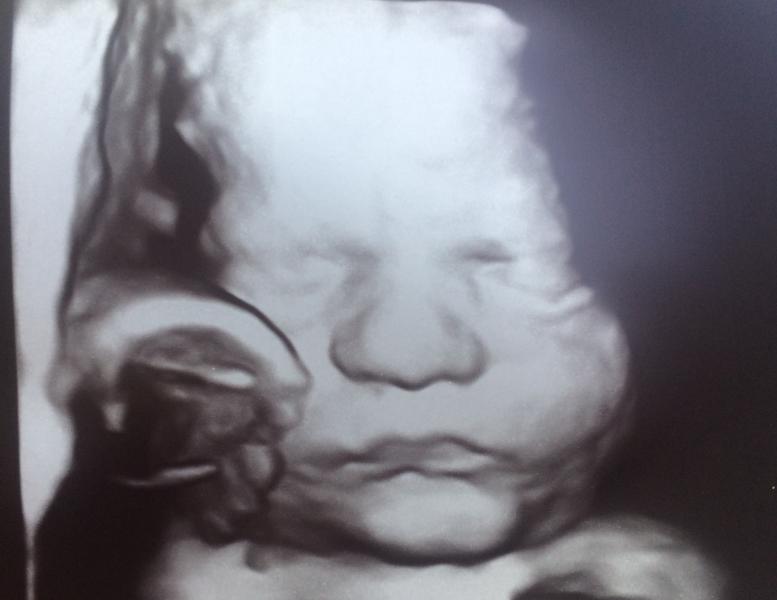

Третий скрининг пройден. Все хорошо у малыша👶🏻

Я переживала, что из-за гсд будет крупненький, но сказали, что что-то щёчки не наел😀2014 весим. Носик картохой, губки бантиком 🤗моя любовь! Все ок 👌🏻

Многоводие правда так и остаётся 😑🙄 что странно, ведь диету соблюдаю...вес за 3 недели стоит, даже немного падает. Короче предположили, что не хватает белка, а углеводы в избытке, хоть и сложные☝🏻